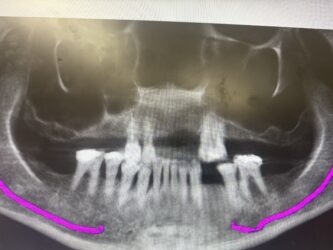

This patient wants implants. We just finished treating her periodontal disease and she is ready for the next phase, however, she has severe bite collapse. In addition, she has uneven ridge in the upper anterior, which would make it challenging esthetically. I asked her dentist to make her a partial denture but the patient kept going back…

I say remove the upper remaining teeth and now the sky is the limit you can do upper denture snap on or all on X ! and that’s it cz if the pt is unreliable and had this much gim disease i don’t know about compliance and orthos ?